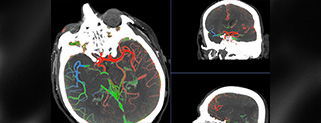

Under de senaste åren har en ny teknik utvecklats för behandling av stroke där man mekaniskt går in och avlägsnar proppen genom så kallad trombektomi, så att blodflödet kan återställas. Detta är exempel på hur minimalt invasiv teknik tillsammans med bildgivande system kan revolutionera diagnos och terapi för en av de stora folksjukdomarna.

- CT imaging today for patient selection for thrombectomy treatment - Sophie Delsart, GE Healthcare